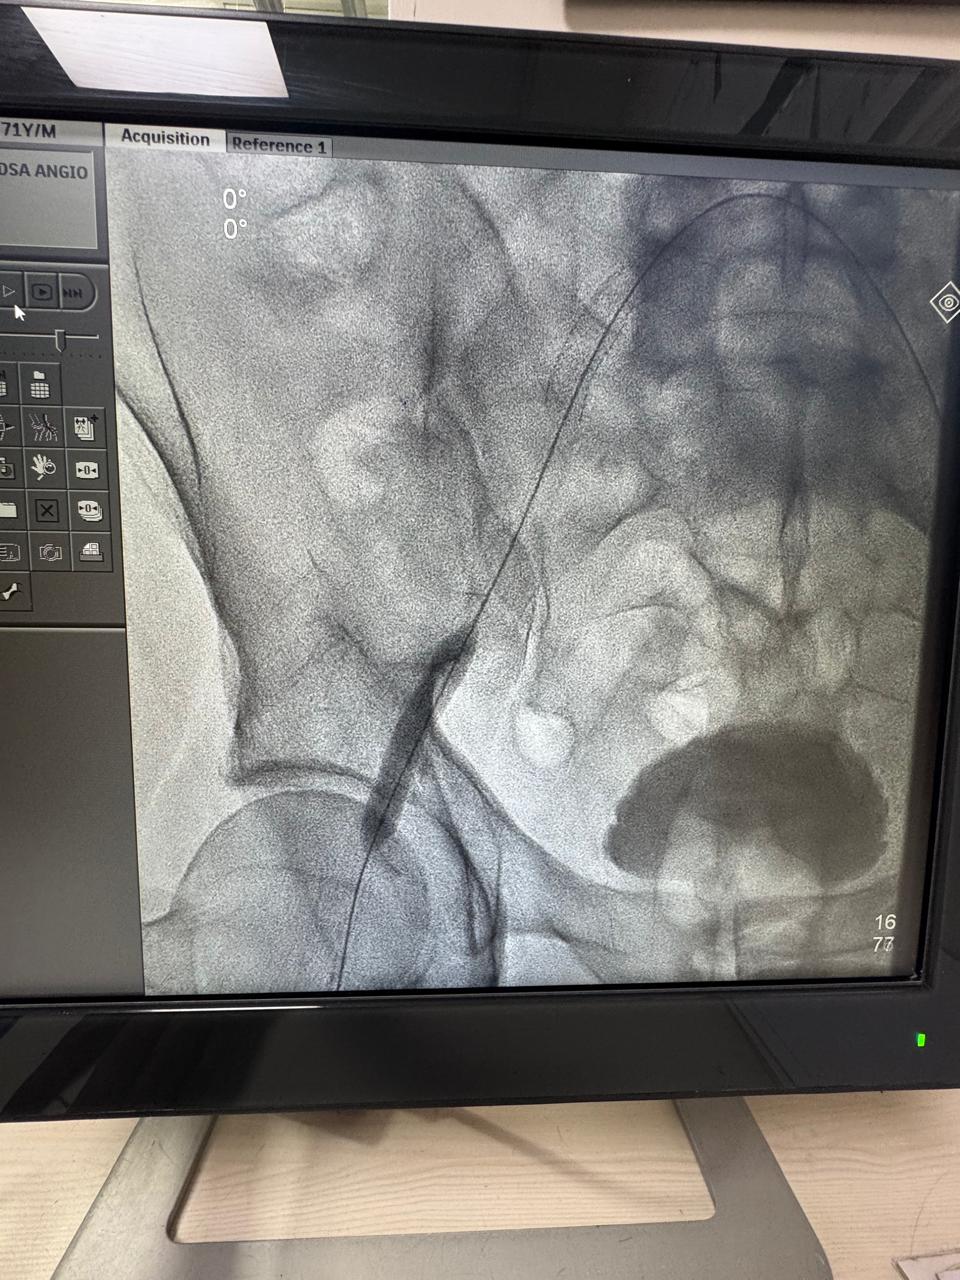

Angioembolization of traumatic right internal iliac artery ( posterior branch)injuries